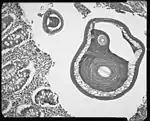

Description

C’est un nématode de 3 à 5 cm de long.